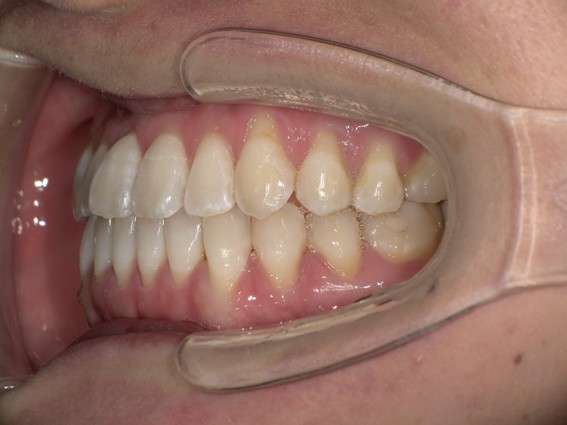

| 主訴 | 口元がでている、口が閉じずらい、上の歯と下の歯のがたつき、顎がない。 |

| 治療内容 | 上下のワイヤー矯正を行いました。 |

以前骨切りを勧められたことがあるという方でしたが、抜歯矯正で口元の突出や顎のしわを改善しました。上唇の厚みや頬の高さを考慮し、老けた印象にならないよう配慮。お顔全体のバランスと年齢に合わせた治療を行いました。